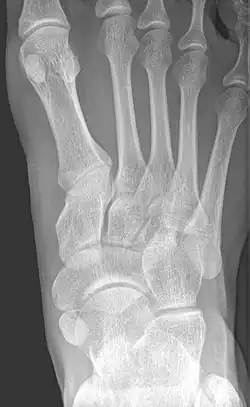

Beim Os tibiale externum (synonym: Os naviculare externum, Os naviculare secundarium, Os naviculare accessorium, Os naviculare bipartitum; englisch accessory tarsal navicular, accessory tarsal scaphoid) handelt es sich um eine häufige (10–16 %) Variation am Kahnbein des Fußes (Os naviculare). In über der Hälfte der Fälle tritt es beidseitig auf.

Es ist eine harte Auftreibung im Sinne eines Überbeins an der inneren Fußwurzel, etwa einen Fingerbreit unter und vor der Innenknöchelspitze, also am Kahnbein, tastbar. Gelegentlich tritt ein Belastungs- und Druckschmerz auf, insbesondere, wenn diese Fehlbildung zusammen mit einem Plattfuß auftritt. Die Diagnose wird mit einem Röntgenbild gesichert.

Es sind drei Formen des Os tibiale externum zu differenzieren:

- Typ 1: Das Os tibiale externum im engeren Sinne ist ein 2–3 mm großes, rundliches Sesambein im Ansatzbereich der Sehne des Musculus tibialis posterior. Es bildet keinen Knorpel zum Kahnbein.

- Typ 2: Das Os tibiale externum ist dreieckförmig und bis zu 9 mm groß. Dieses hat eine Knorpelverbindung zum Kahnbein. Dieser Typ ist mit über 50 % der häufigste. Es handelt sich um eine unterbliebene Verschmelzung der Knochenkerne, aus denen sich das Kahnbein in der frühen Jugend bildet.

- Typ 3: Hier ist das Kahnbein anlagemäßig weit ausladend nach innen ausgebildet (Os naviculare cornutum, englisch cornuate navicular). Hier ist im Gegensatz zu den ersten beiden Formen kein Spalt auszumachen.